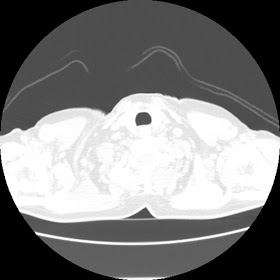

A 62 years old man with enlarged mole on chest since 2 months.

CT chest :-